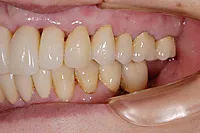

■治療前

■治療後

| 主訴 | しっかりかみたい(咬合障害) |

| 治療方法 | 費用を抑える為、全てインプラントではなく、インプラントを土台とした入れ歯の治療 |

| 治療期間 | 約6か月 |

| 通院回数等 | 約20回 |

| 費用 | 約150万円 |

| リスク・副作用 | 術後の腫れ・痛み |